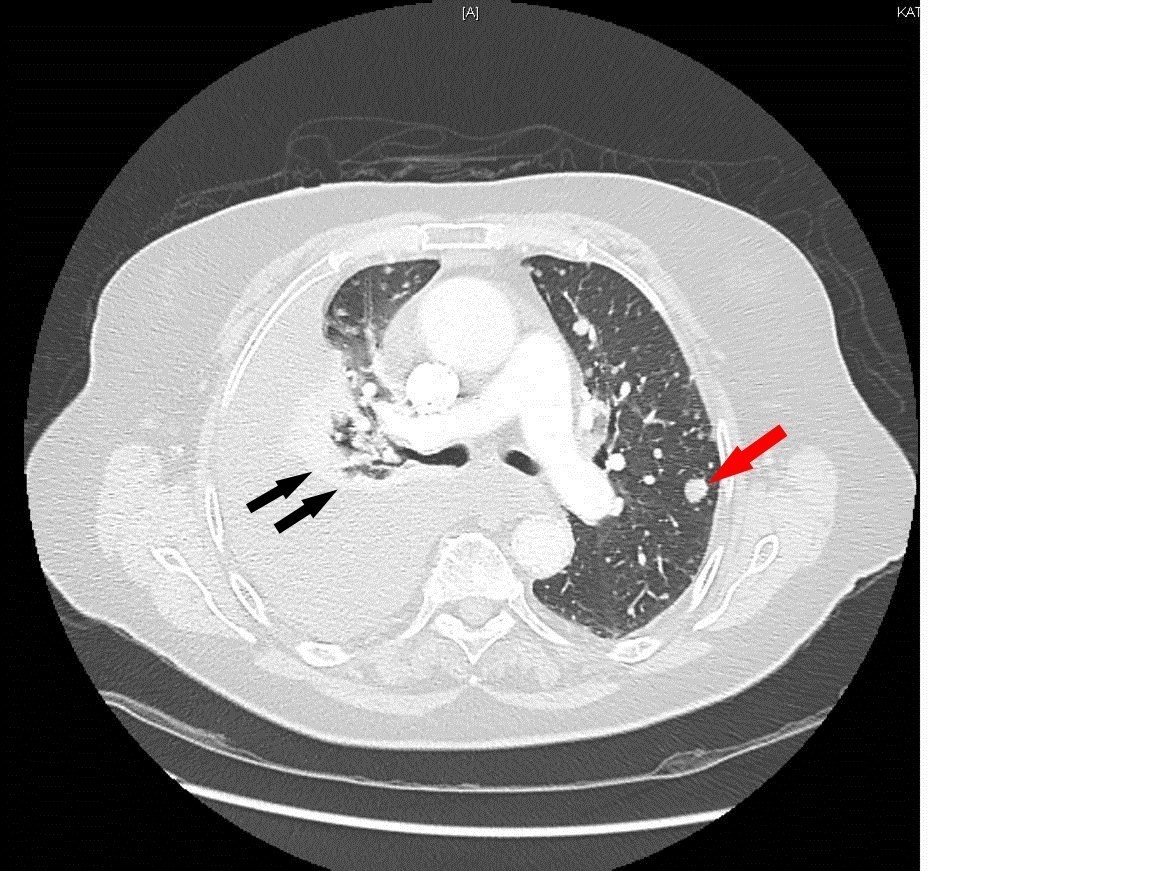

Mme K. est admise aux urgences pour exploration d’une douleur thoracique. Cette femme de 76 ans est suivie en cardiologie depuis dix ans pour un rétrécissement aortique, une hypertension artérielle (HTA) et une dyslipidémie. Elle est parfaitement autonome à domicile. Elle fume un demi-paquet de cigarettes par jour depuis trente ans. Elle est traitée par rivaroxaban (anti-Xa) depuis six semaines pour une thrombose veineuse profonde (TVP) du membre inférieur droit survenue à l’occasion d’un voyage en voiture. Le reste de son traitement comporte de la simvastatine et de l’hydrochlorothiazide.

Depuis trois jours, elle présente une douleur thoracique croissante, latéralisée à droite et survenue sans facteur déclenchant évident.

À évoquer en priorité car TVP récente et douleur thoracique. Le traitement anticoagulant en cours n’élimine pas une migration embolique (surtout en cas de mauvaise observance).

À évoquer devant une douleur thoracique latéralisée.

À évoquer devant une douleur thoracique latéralisée chez une patiente avec tabagisme important.